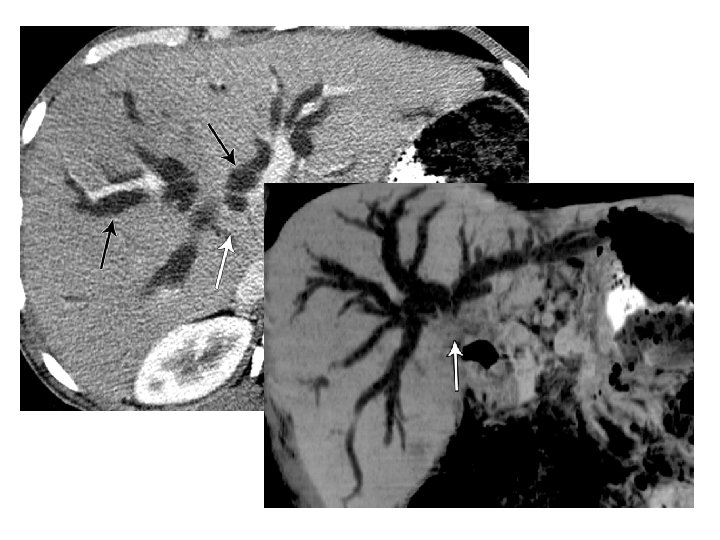

ALGORITMO DIAGNÓSTICO ICTERICIA OBSTRUCTIVA ULTRASONOGRAFÍA ECO DOPPLER � Dilatación de la vía biliar SI NO Baja probabilidad Sospecha de COLANGIOCARCINOMA Alta probabilidad / Lesión PET-TC TC Angio/ Portografía / Venografía CONTROL OTROS Congénita Colangitis Estenosis sin masa Coledocolitias is US ESTADIFICA R TRATAMIENTO PAAF/biopsia US TC Eco-Endoscopia + PAAF Arteriografía RM + CPRM Confirmación diagnóstica Angio. RM RM + CPRM Sainani NI et al. Cholangiocarcinoma: current and novel imaging techniques. Radiographics 2008. 28: 1263 -1287